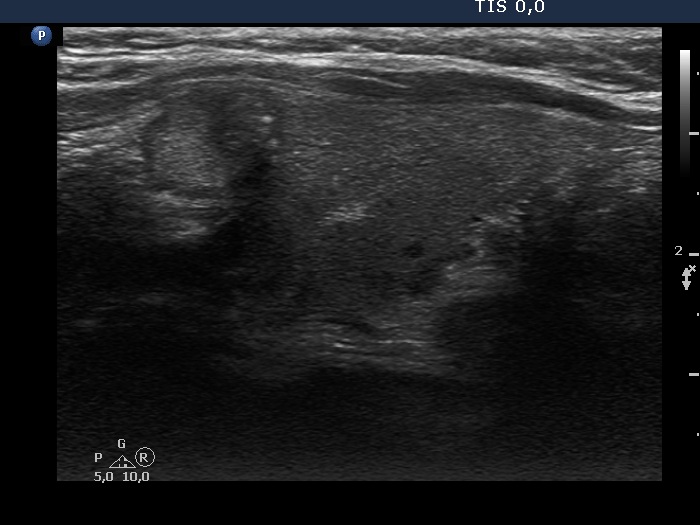

Study on 100 consecutive patients with thyroid nodule - case 087 (ultrasonographic picture 11)

Left lobe, transverse scan. There is a lymph node lateral to the carotid artery.